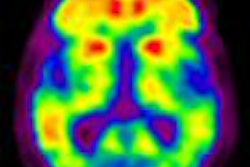

Duke MMIL designs novel SPECT/CT system for 3D breast imaging